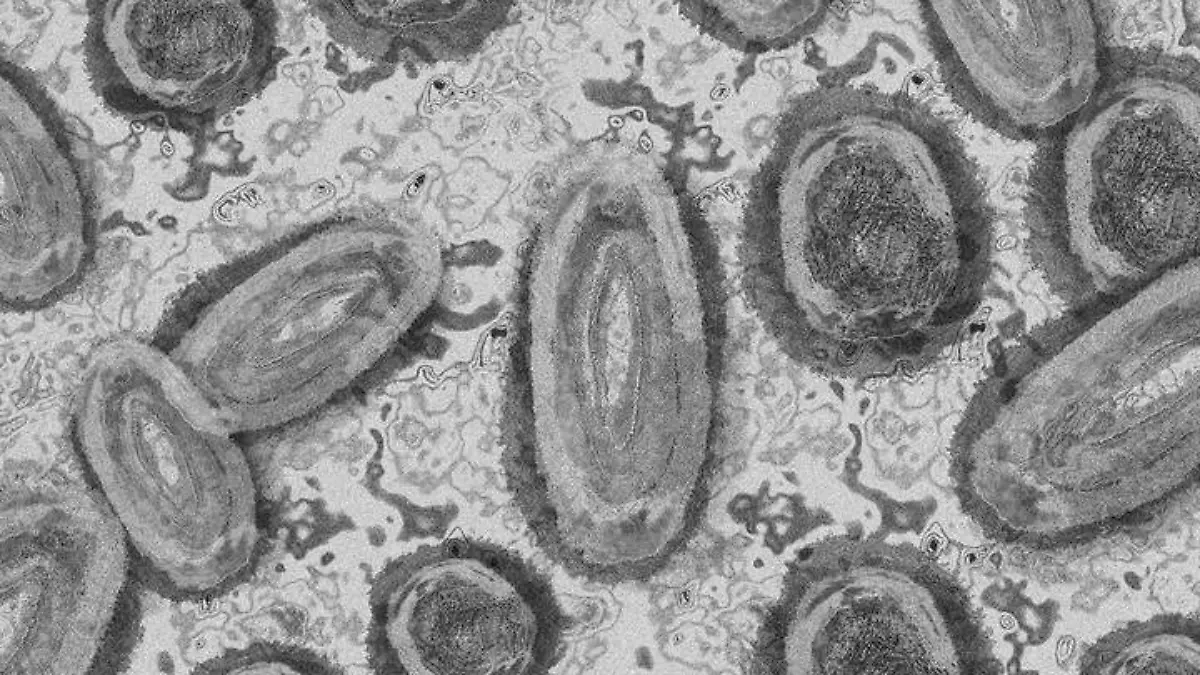

Viruela del Mono llega a Sonora; Secretaría de Salud confirma dos casos

Dos personas residentes de Puerto Peñasco y Caborca fueron confirmadas con la viruela símica por la Secretaría de Salud durante la noche de este miércoles.